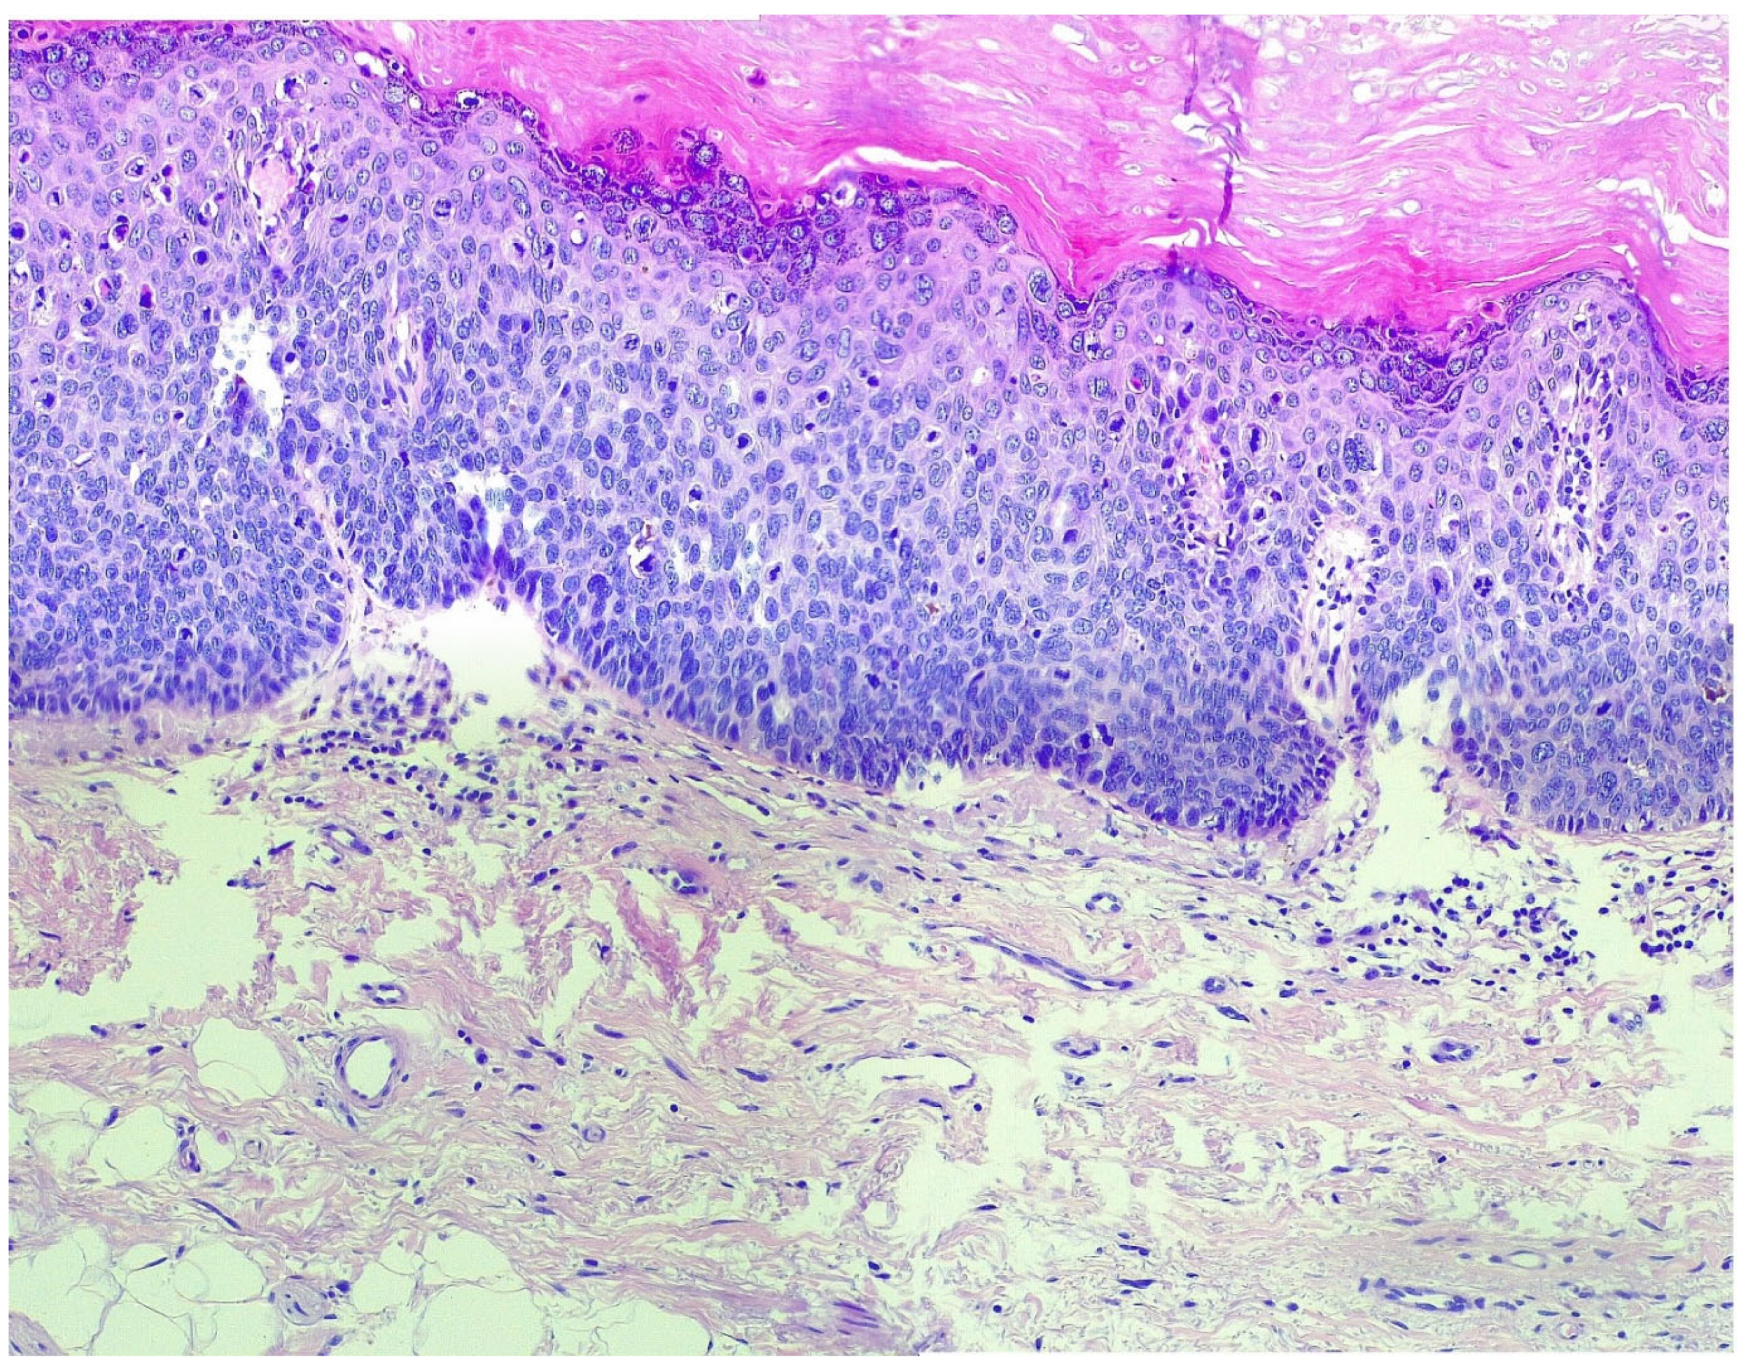

The Clinical Management and Outcomes of Two Cases of Vulvar Neoplasms: A Two-Case Study of VIN 3 and Stage IA Vulvar Keratinizing Squamous Cell Carcinoma

2.2. Patient B